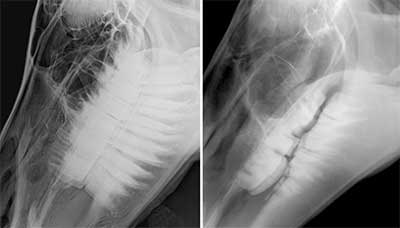

When things don’t line up properly, the wear patterns can be even more dramatic, causing malocclusions. “When all the upper maxillary cheek teeth arcades aren’t in alignment with all the lower mandibular cheek teeth, it can lead to part of a tooth not having an opposing tooth to grind against, and therefore the tooth will keep erupting and develop overgrowths.” An example of this is what is known as “parrot mouth.”

Parrot mouth occurs when the mandible is sitting back behind and the maxillary incisors extend out over the mandibular incisors. “The horse develops a ramp and a hook, and usually the incisors don’t line up either, so you’ll get an overgrowth of one or both. You might say, ‘Well, what’s the problem with that?’ Eventually, the ramps will dig into the soft tissue. The problem with this kind of anatomy, this malocclusion, is that it prevents the normal rostral caudal movement of the mandible – sliding forward and back – with the flexion of the head. When you have a hook and a ramp and uneven incisors, that locks the jaw and usually transfers to temporomandibular pain.” Riders will notice that the horse resists the bit, especially when asked to flex at the poll.